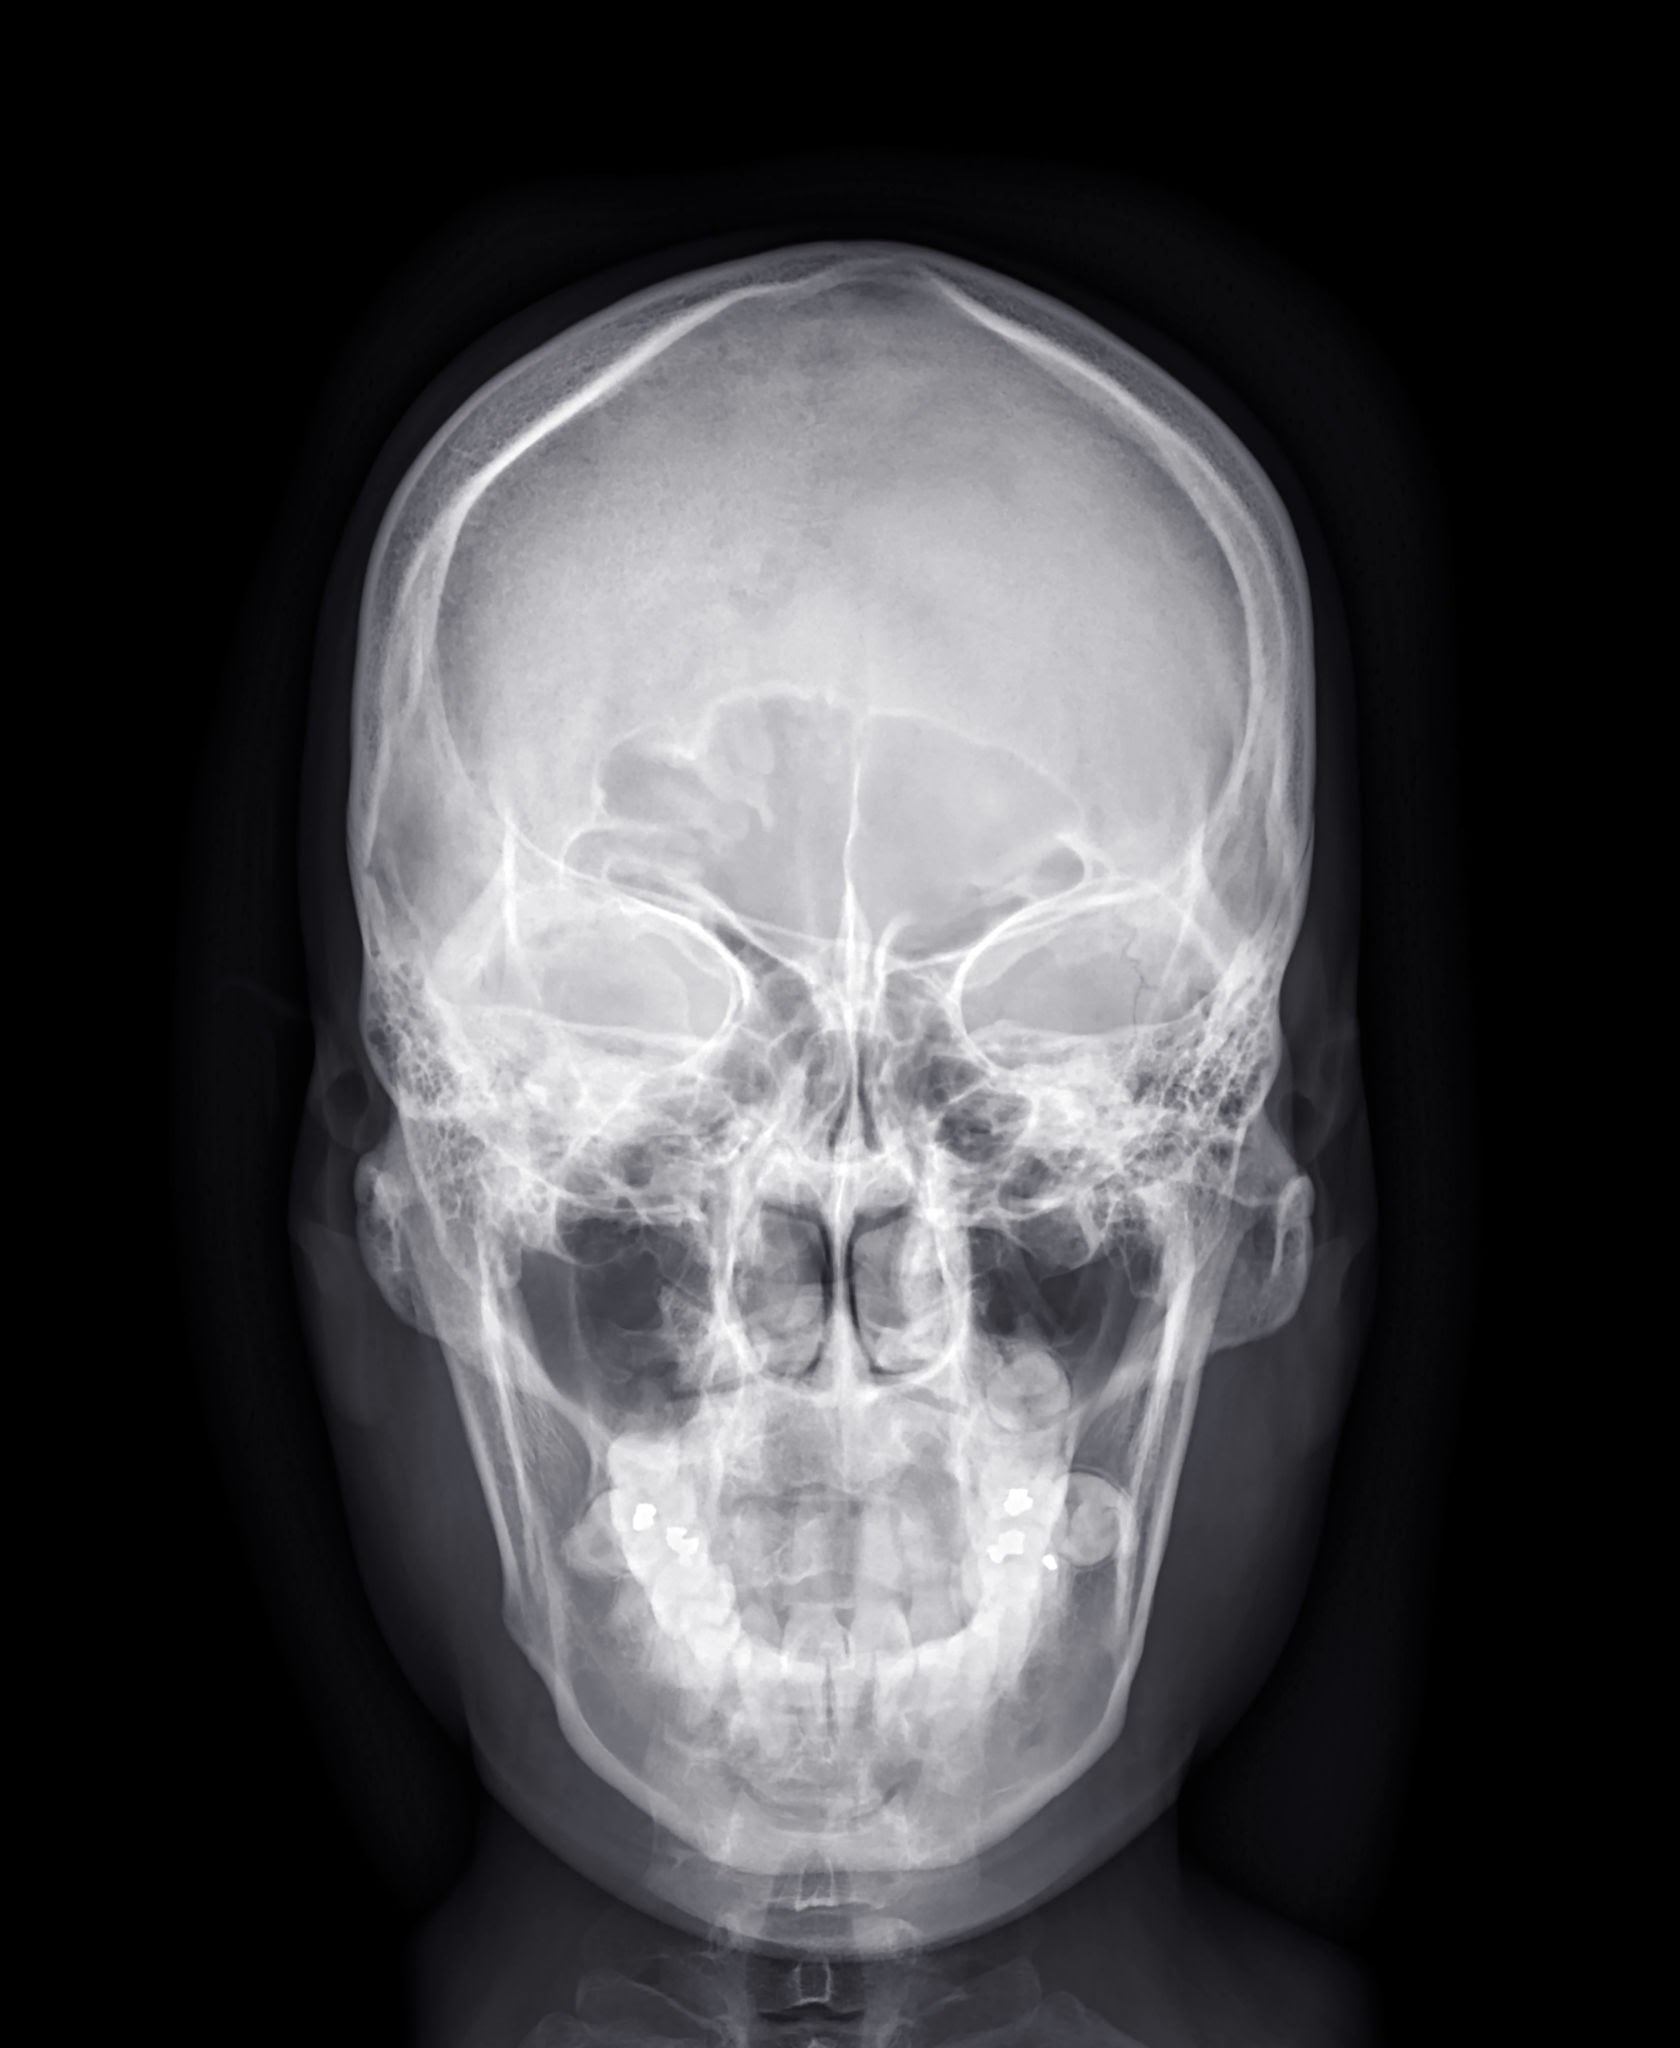

AP View (Anteroposterior View) refers to a type of X-ray imaging where the X-ray beam passes from the front (anterior) of the body to the back (posterior). This is commonly used when the patient is unable to stand or when a frontal view is required but the standard PA (posteroanterior) view isn’t feasible due to the patient’s condition. In diagnostic centers, AP views are frequently used for chest, abdomen, pelvis, and limb examinations, especially for bedridden or trauma patients. The image produced helps radiologists assess the internal organs, bones, or tissues from a front-to-back perspective. However, it is important to note that the AP view may slightly magnify certain structures like the heart, which is why the PA view is preferred for routine chest X-rays when possible.

AP View